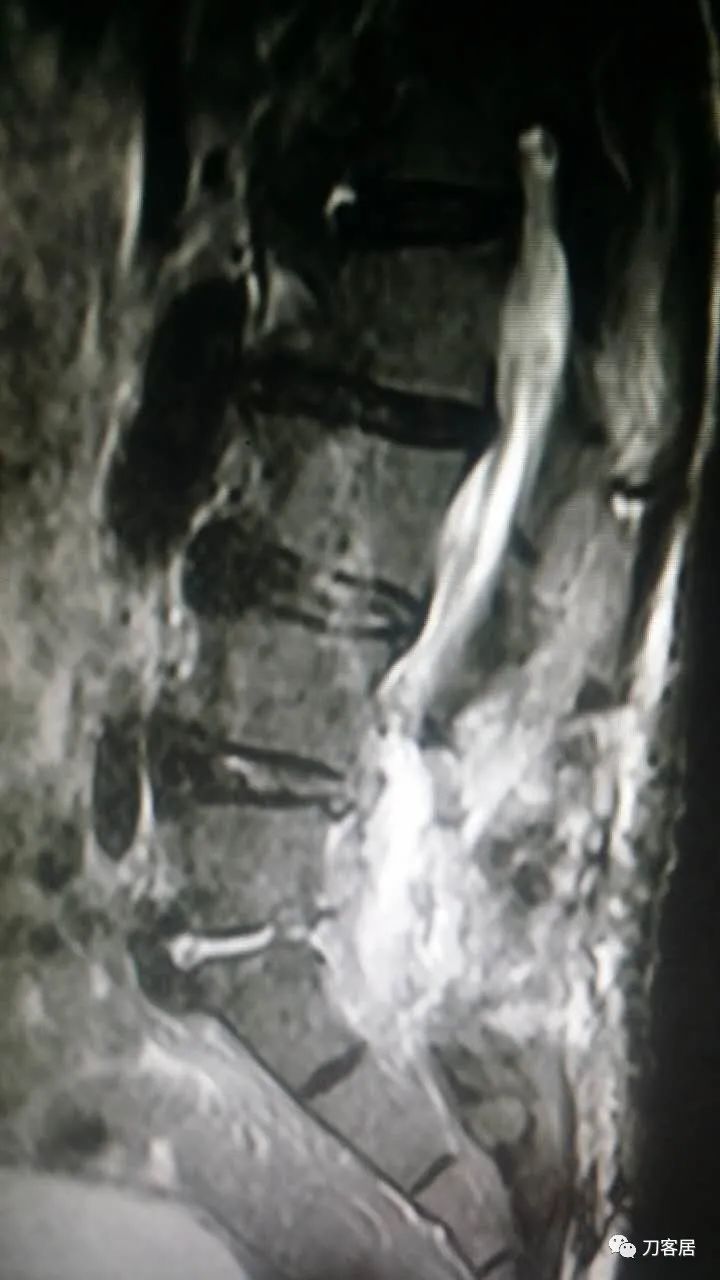

加注图14. 胸9-10椎管内后方高信号占位病变,考虑血肿形成。

加注图15. 胸9-10椎管内后方高信号占位病变,考虑血肿形成。

加注图16. 胸9-10椎管内后方高信号占位病变,考虑血肿形成。

加注图17. 胸9-10椎管内后方高信号占位病变,考虑血肿形成。

胸椎管内也有血肿[流泪] ,我要奔溃了,T9中段到10也有,偏左侧。